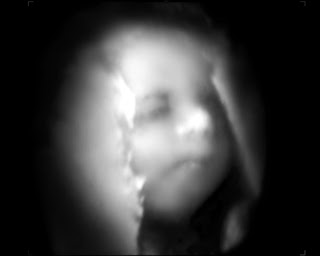

And finally, for your viewing pleasure, my baby’s last picture before s/he is born: